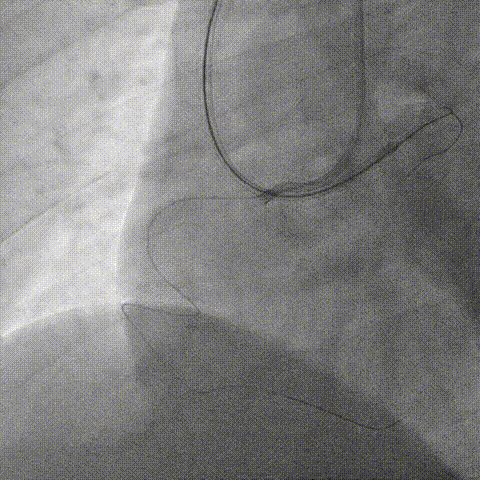

最终逆向更换Judo 6,但导丝仍进入内膜下、在逆向导丝指引下,正向选择Judo 6、LAD近段严重成角,最终Judo 6 在LAD中段与逆向Judo 6靠近

尝试反向CART技术,但1.5mm球囊无法进入严重钙化段,在正向Expressman支撑下,先后使用1.25mm, 1.0mm球囊,最高24atm

再换用2.0, 2.5球囊扩张、但仍无法完成AGT技术,遂使用3.0球囊,最终逆向导引钢丝进入正向指引导管内